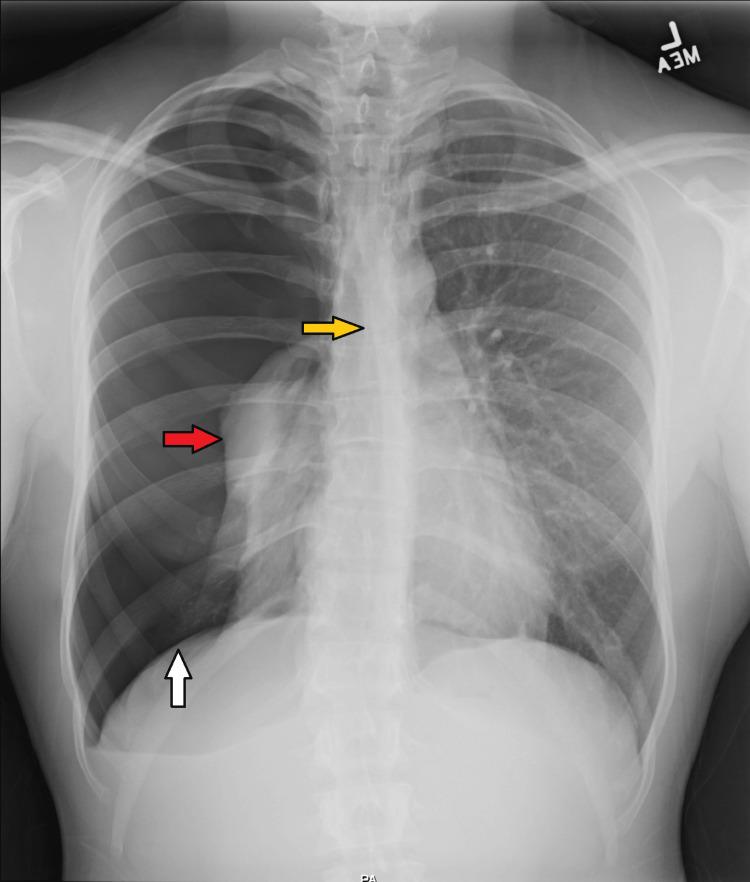

A pneumothorax is a medical condition characterized by the presence of free air in the pleural cavity. Pneumothorax can be classified as spontaneous, traumatic, or iatrogenic. Spontaneous pneumothorax sustained from a jiu-jitsu-induced blunt trauma has not been described in any sports literature. This case report involves a 26-year-old male athlete who presented to the emergency room complaining of right-sided chest pain in the recumbent position and shortness of breath upon exertion. Breath sounds were diminished on the right with hyper resonance to percussion. Inspection of the chest revealed diffuse erythema on the right side. A chest X-ray revealed a right tension pneumothorax that was treated with a 20-French chest tube. This report aims to highlight the importance of recognizing the possibility of pneumothorax in jiu-jitsu athletes, implementing early treatment, and exploring potential causes of pneumothorax in otherwise healthy individuals.

气胸是一种以胸膜腔内存在游离气体为特征的医学状况。气胸可分为自发性、创伤性或医源性。柔术导致的钝性创伤引起的自发性气胸在任何体育文献中均未被描述过。本病例报告涉及一名26岁男性运动员,他到急诊室就诊,主诉卧位时右侧胸痛,用力时呼吸急促。右侧呼吸音减弱,叩诊呈过清音。胸部检查发现右侧弥漫性红斑。胸部X光显示右侧张力性气胸,通过一根20法式胸管进行了治疗。本报告旨在强调认识到柔术运动员发生气胸的可能性、实施早期治疗以及探究健康个体发生气胸潜在原因的重要性。